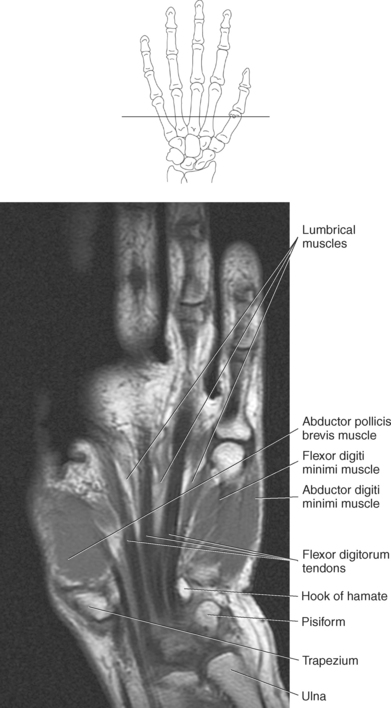

The numerous muscles of the forearm become tendinous just before the wrist joint. The many tendons located in the wrist can be divided into palmar and dorsal tendon groups (Figures 9.120, A and B and 9.127). The palmar tendon group collectively flexes the fingers and wrist. As this group courses through the carpal tunnel, the tendons appear to be arranged in two discrete rows (Figures 9.118, A and 9.119). The tendons of the dorsal tendon group, spanning the superficial surface of the wrist, are considered the extensors of the fingers and wrist (Figures 9.128 through 9.140).

The muscles of the hand can be divided into three groups: (1) metacarpal group (muscles of the metacarpals considered to be the central muscles of the hand), (2) thenar group (muscles involving the thumb and creating the thenar eminence on the radial side), (3) hypothenar group (muscles involving the fifth digit and creating the hypothenar eminence on the ulnar side). These muscles are demonstrated in Figures 9.128 through 9.143.

The metacarpal muscle group includes the interossei and lumbrical muscles. There are seven short interossei muscles in the metacarpal muscle group: three single-headed muscles located on the palmar surface and four double-headed muscles located on the dorsal surface (Figure 9.141, A and B). The four palmar interossei muscles arise from the first, second, fourth, and fifth metacarpals and insert on the corresponding proximal phalanges, frequently radiating into the corresponding tendons of the dorsal aponeurosis. These muscles are responsible for flexion at the MCP joints and extension at the interphalangeal joints. The dorsal interossei arise by two heads from the sides of the five metacarpal bones to insert on the proximal phalanges and radiate onto the dorsal aponeurosis. Like their palmar counterparts, the dorsal interossei flex at the MCP joints and extend at the interphalangeal joints. The four small lumbrical muscles arise from the tendons of the flexor digitorum profundus and pass to the radial side of the corresponding finger to insert on the extensor expansion covering the dorsal surface of the finger (Figure 9.142). The lumbricals flex the first phalanges at the MCP joints and extend the second and third phalanges at the interphalangeal joints.

The four muscles of the thenar group are the abductor pollicis brevis, flexor pollicis brevis, adductor pollicis, and opponens pollicis. The abductor pollicis brevis is a thin, flat superficial muscle arising from the transverse carpal ligament, navicular, and trapezium (Figure 9.143). It runs inferiorly and laterally to insert on the base of the first phalanx of the thumb to abduct the thumb. The flexor pollicis brevis has two heads: The superficial or lateral head arises from the flexor retinaculum, and the deep or medial head arises from the trapezium, trapezoid, and capitate. This muscle inserts on the radial and ulnar base of the first phalanx to flex, adduct, and abduct the thumb (Figure 9.143). Frequently, a sesamoid bone can be found in the insertion tendon on the radial side. The adductor pollicis also has two heads: The transverse head arises from the dorsal aspect of the third metacarpal, and the oblique head arises from numerous slips off the capitate, bases of the second and third metacarpals, and the sheath of the flexor carpi radialis tendon. The adductor pollicis inserts onto the base of the first phalanx of the thumb to provide adduction and assist in the opposition and flexion of the thumb (Figures 9.142 and 9.143). The opponens pollicis provides the main opposition for the thumb but also assists with adduction. It arises from the trapezium and flexor retinaculum and inserts onto the radial aspect of the first metacarpal (Figures 9.142 and 9.143). These muscles are also demonstrated in sequential Figures 9.128 through 9.140.

The hypothenar group consists of three muscles: abductor digiti minimi, flexor digiti minimi brevis, and opponens digiti minimi. The abductor digiti minimi muscle arises from the pisiform and the flexor retinaculum to end in a flat tendon that inserts onto the ulnar base of the first phalanx of the little finger (Figures 9.142 and 9.143). The abductor digiti minimi muscle is the main abductor of the little finger. The flexor digiti minimi brevis muscle arises from the flexor retinaculum and the hook of the hamate. It fuses with the tendon of the abductor digiti minimi to insert on the base of the first phalanx of the fifth digit (Figures 9.142 and 9.143). The flexor digiti minimi brevis flexes at the MCP joint. Like the flexor digiti minimi brevis muscle, the opponens digiti minimi arises from the hook of the hamate and the flexor retinaculum (Figure 9.143). It inserts on the ulnar surface of the fifth metacarpal to bring the little finger into the position for opposition. For the hand muscles, see Figures 9.128 through 9.140.